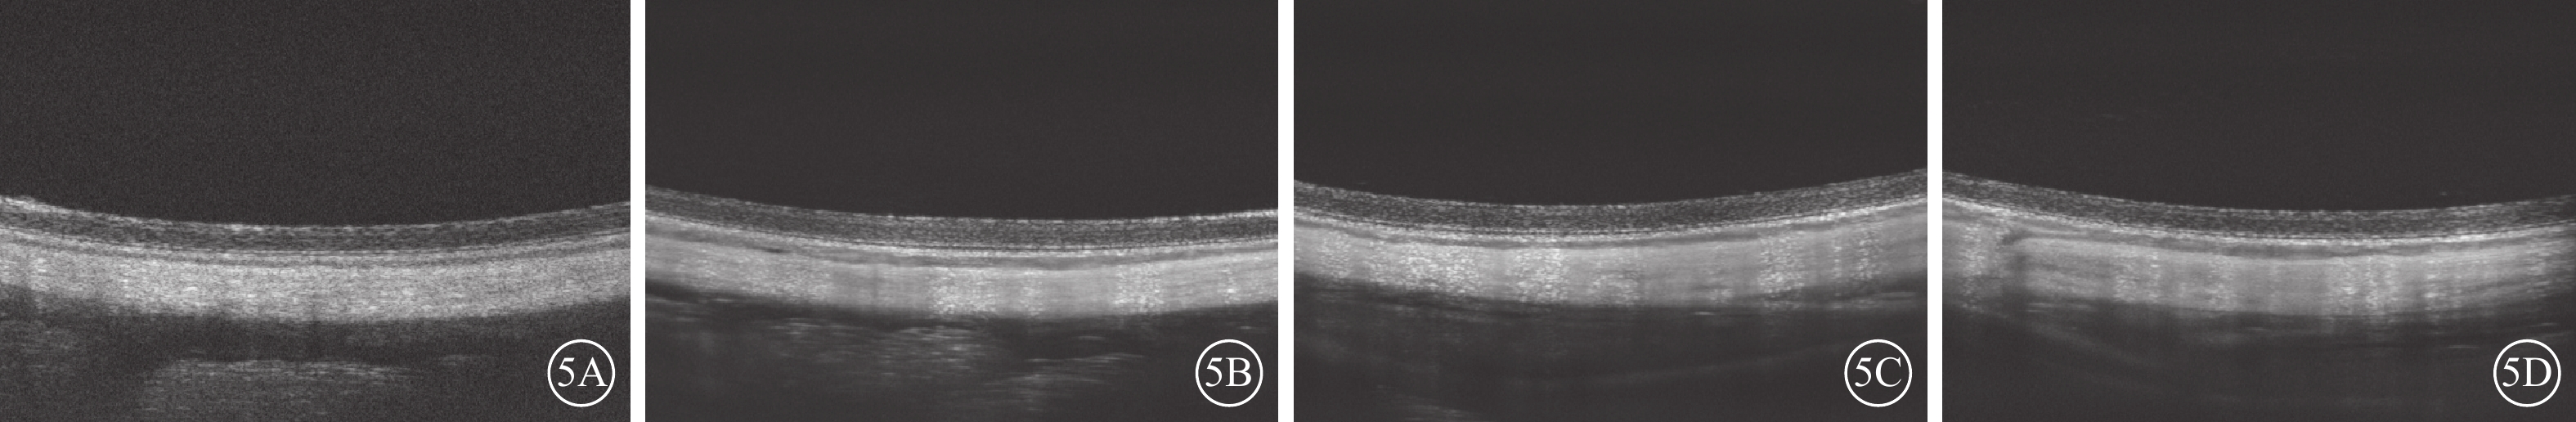

兔眼連續IVG后1周,與IVG前比較,小劑量實驗組、大劑量實驗組兔眼視網膜均未見出血、滲出(圖4);視網膜各層結構清晰連續,未見視網膜水腫或其他結構異常(圖5)。